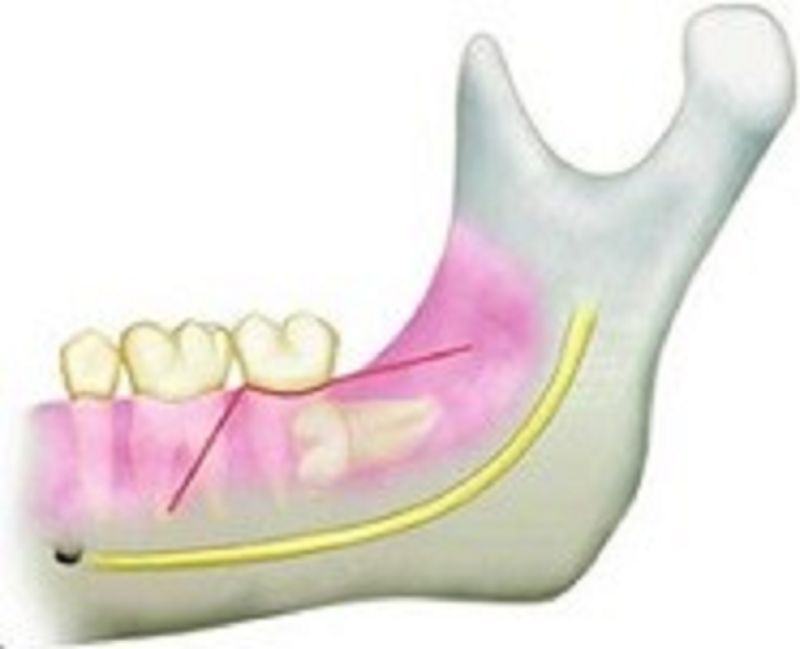

35. Cut releasing incisions to avoid cutting through the mental nerve?

Cut releasing incisions mesial of the 4 or distal of the 6

Cut releasing incisions mesial of the 5 or distal of the 6

Cut releasing incisions mesial of the 4 or distal of the 5

All are correct